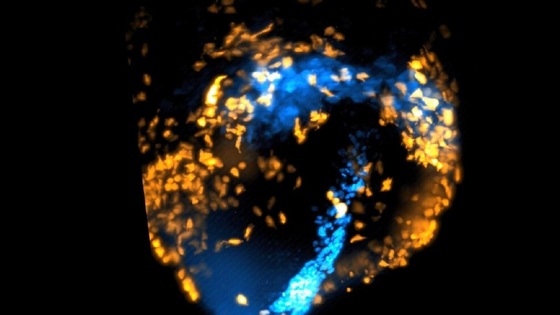

Покадровая 3D-видеосъемка велась внутри живого мышиного эмбриона. Его выращивали в лаборатории в чашках Петри.

Видеосъемка велась с использованием технологии усовершенствованной микроскопии плоскостного освещения. Она позволяет с помощью полосы света вести 3D-съемку, не нанося при этом вред тканям.

Съемка велась в течение 40 часов, а кадры делались каждые две минуты. В результате на них видно, как клетки сердца (кардиомиоциты) заранее помеченные флуоресцентными маркерами, начинают спонтанно организовываться в предсердия и желудочки. При этом их путь можно отследить с самого начала.